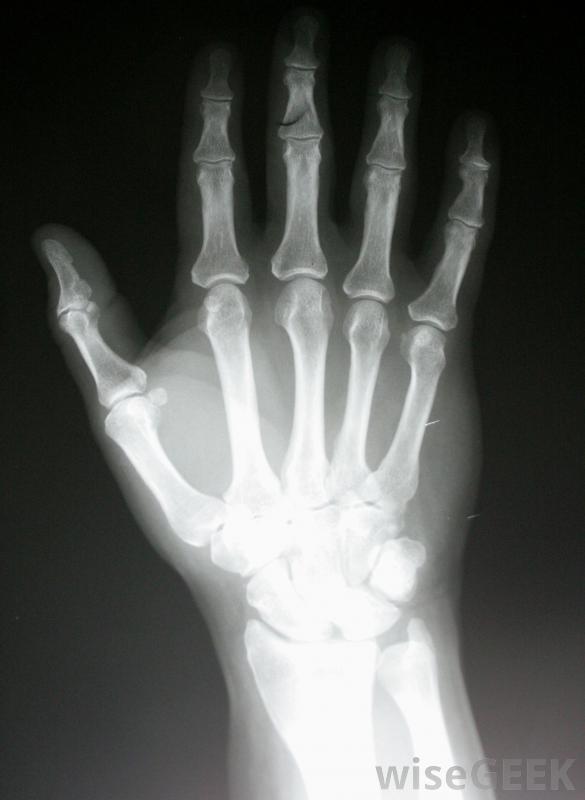

SAPHO綜合征是一種罕見的疾病,可以引起嚴重的骨骼,關節和皮膚問題。縮寫是該病的五個主要組成部分:滑膜炎、痤瘡、膿皰病、骨質增生和骨炎。并不是所有的患者都有這種癥狀,而且病情的嚴重程度可能范圍很廣。癥狀可能包括關節僵硬、背部僵硬疼痛,行動不便,以及各種皮膚問題。治療決定是根據患者的具體癥狀做出的,但通常包括每天服用消炎藥和使用外用面霜。X光片可能會顯示出骨炎癥和不尋常的生長模式。SAPHO綜合征的病因尚不清楚。懷疑至少部分是一種自身免疫性疾病,即人體自身免疫系統錯誤地攻擊健康的骨骼、皮膚,以及關節組織。醫生不確定這種疾病是否是遺傳的,因為它非常罕見,而且大多數病例似乎不是家族遺傳的。沒有傳染源或特定的環境毒素與SAPHO綜合征有關。任何年齡都可能出現癥狀,但通常見于中老年人由于膿皰病,手上可能會形成水泡SAPHO綜合征的每一個成分都會引起獨特的癥狀和健康問題滑膜炎的特征是身體關節和脊柱的炎癥、腫脹和疼痛。痤瘡在薩福綜合征患者中往往很嚴重,并且經常會在面部和上背部爆發。膿皰病是另一種皮膚并發癥,會導致手、腳或身體其他部位出現水皰和膿皰SAPHO綜合征的癥狀可能包括背痛。骨骼疾病往往是導致患有骨質增生癥。骨質增生是一種骨組織過度生長,可發生在脊柱下部、腿部、手臂或身體其他部位。它會引起疼痛和極大地限制靈活性。骨炎或骨炎癥通常伴隨骨質增生而加重癥狀局部使用皮質類固醇軟膏有助于緩解與SAPHO綜合征相關的疼痛和腫脹。專家小組可能參與確定診斷皮膚狀況通常可以通過體格檢查來確定,而診斷性的影像學掃描如x光片可以顯示出骨炎、異常的生長模式和關節受累。血樣可以被分析以排除其他潛在的病因,如感染和更為人所知的自身免疫性疾病滑膜炎是SAPHO的一種,其特征是炎癥、腫脹,以及身體關節和脊柱疼痛。大多數皮膚并發癥患者都會使用局部皮質類固醇軟膏來緩解疼痛和腫脹。異維甲酸通常用于治療慢性痤瘡,阿維a是用來治療膿皰病的。口服類固醇和其他消炎藥可以幫助緩解骨頭酸痛和關節僵硬。此外,患者可能會被要求限制活動水平,并參加定期的物理治療,以安全地恢復骨骼力量。SAPHO綜合征通常可以得到治療當病人堅持他們的治療計劃時有效。檢查X光片可以幫助醫生診斷SAPHO痤瘡在SAPHO患者中往往很嚴重,并可能導致疤痕。那些患有SAPHO綜合征的人經常患有痤瘡。